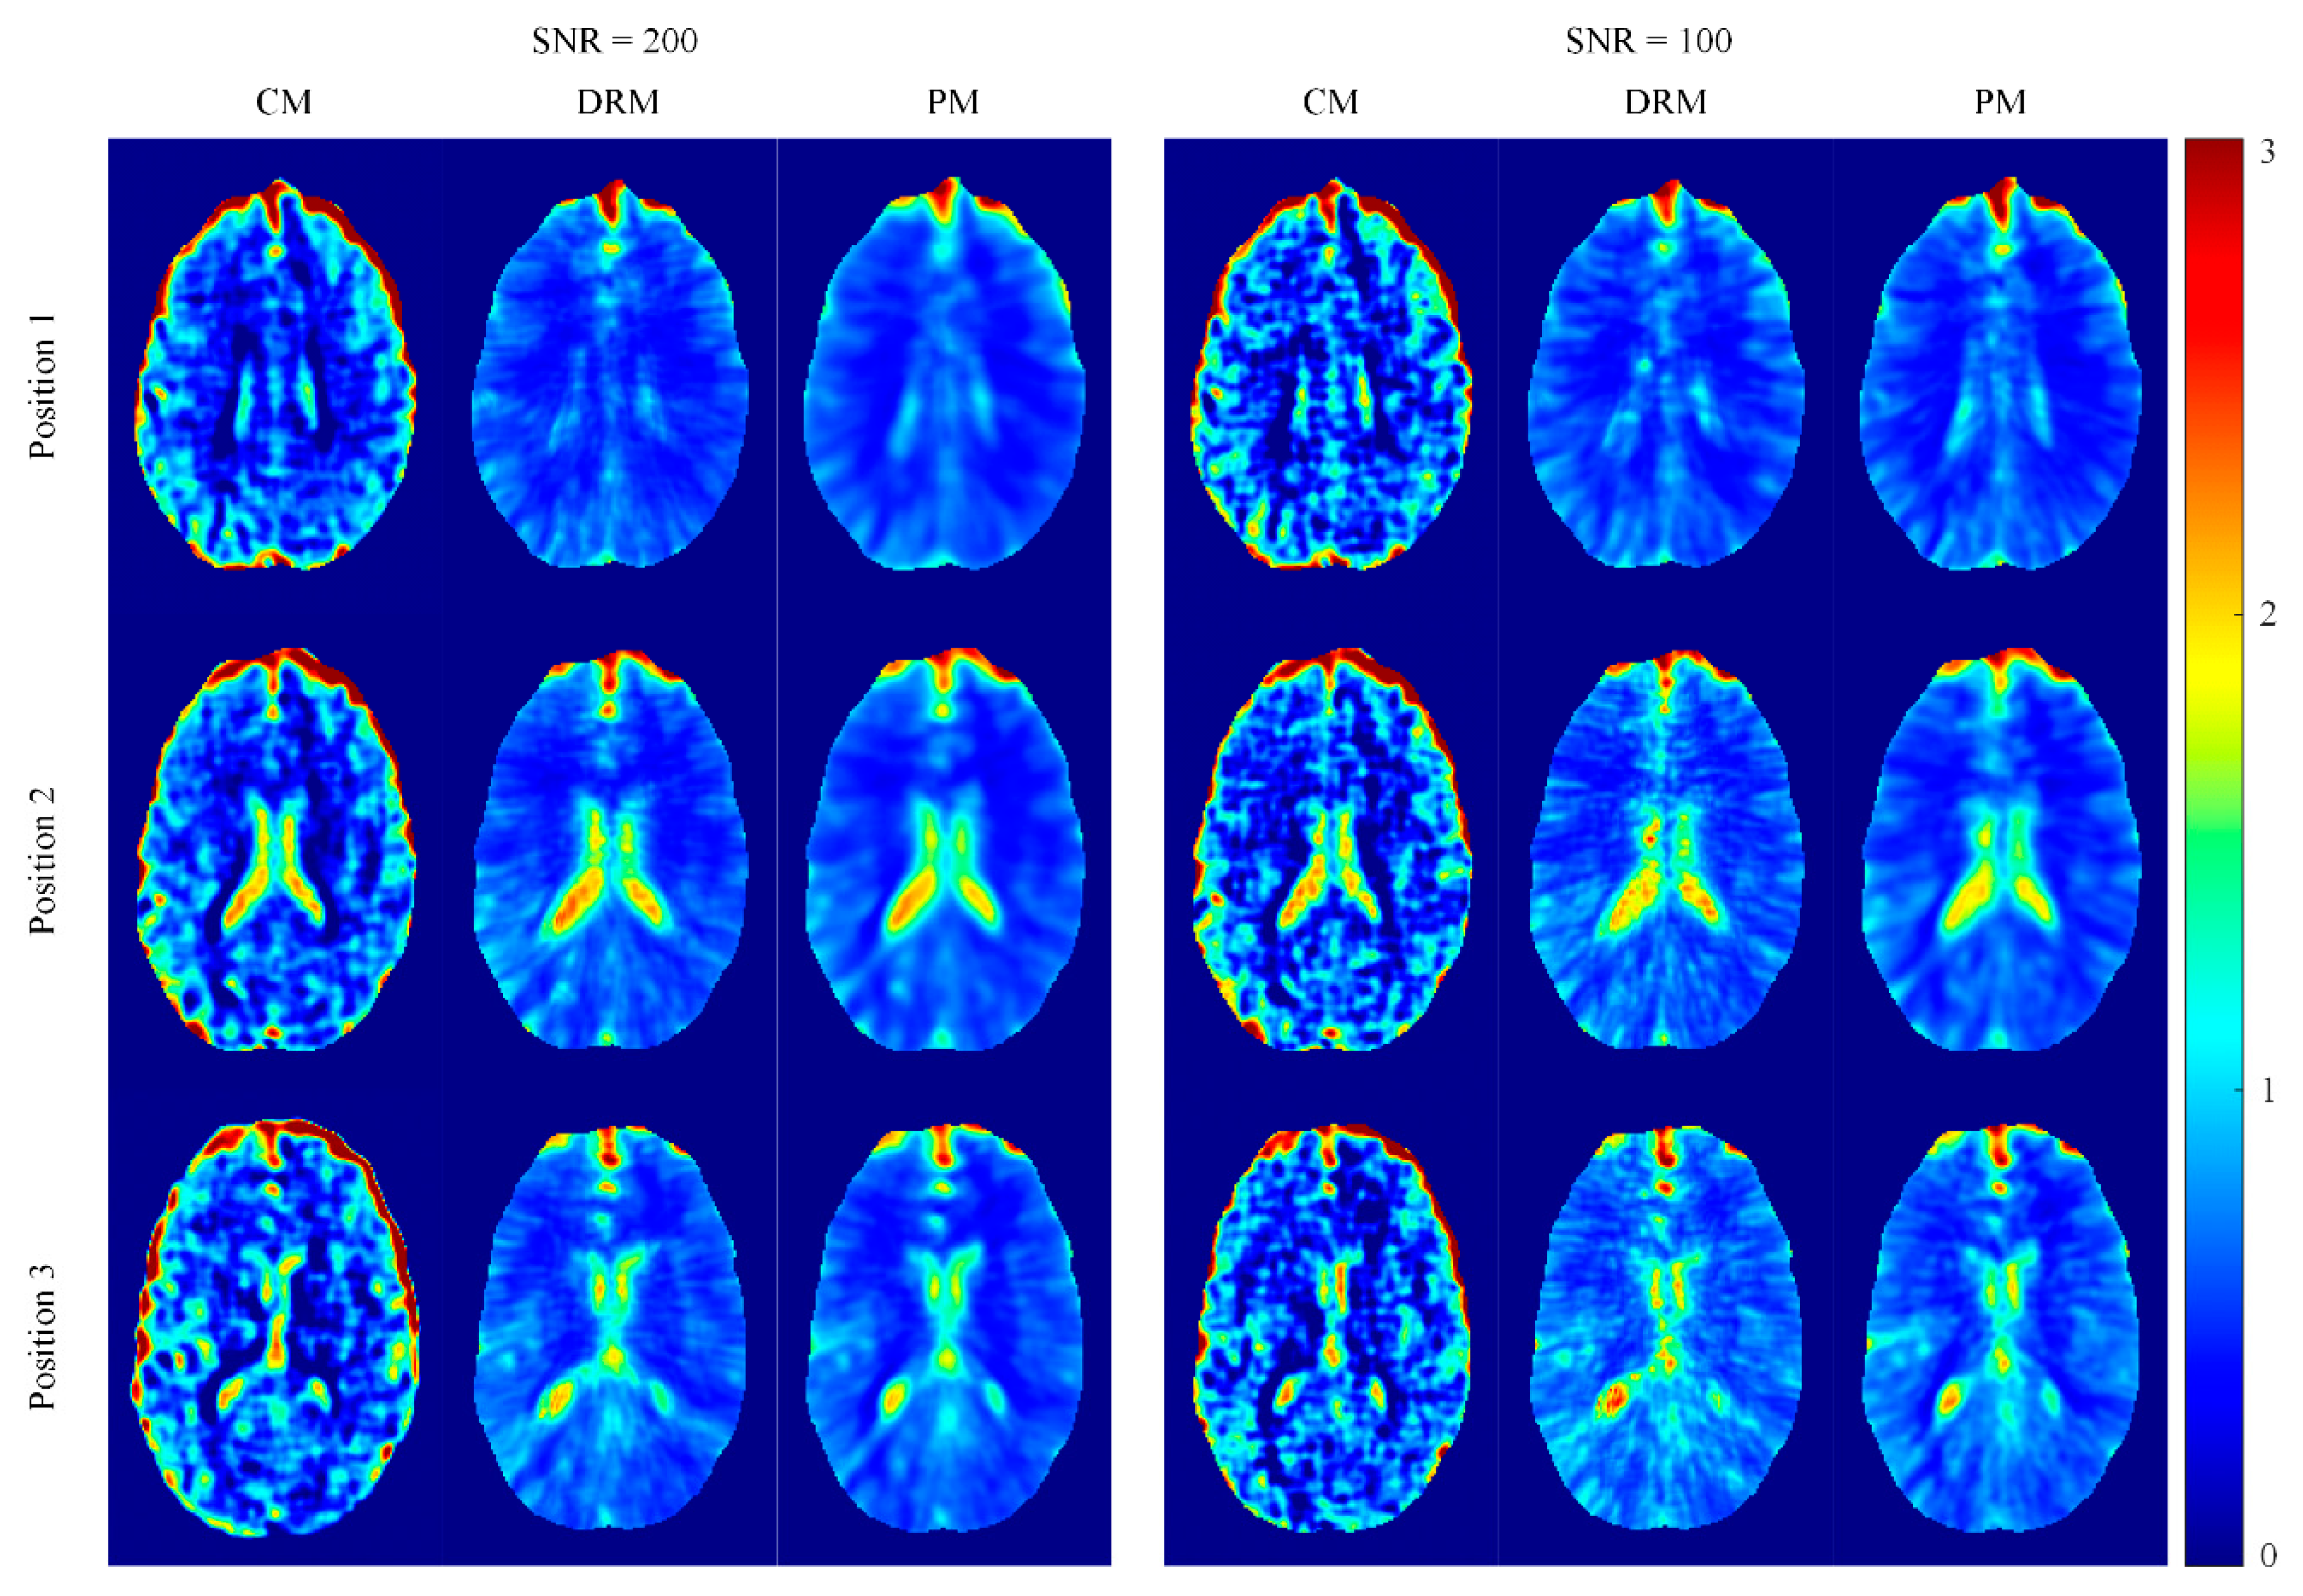

4.1. Phantom Simulation Results

4.2. Ella Head Simulation Results